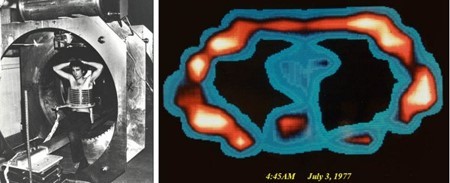

Pas in 1977 slaagde R. Damian erin het eerste beeld/foto van het menselijk lichaam te creëren. De resolutie was nog niet voldoende voor diagnostisch gebruik en de opnametijden namen nog enkele uren in beslag. In 1981 kon voor het eerst tumorweefsel worden onderscheiden van gezond weefsel. MRI werd in toenemende mate klinisch geaccepteerd, onder andere vanwege de voordelen, zoals het hoge contrast van de weke delen (bot versus zacht weefsel, zoals spieren) en het gebrek aan blootstelling aan schadelijke straling. In de begintijd van MRI moesten patiënten vaak meerdere keren worden onderzocht. Na veelvuldige MRI-onderzoeken meldden veel patiënten met gewrichtsproblemen, zoals artrose (gewrichtsslijtage) -aanvankelijk onverklaarbaar voor artsen- dat hun klachten waren verminderd en dat enkelen zelfs symptomenvrij werden.